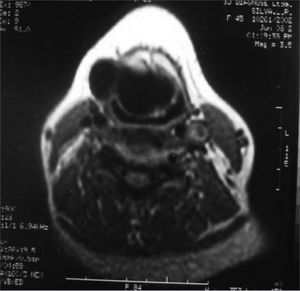

CASE REPORTOur patient was a 45 year old female, housewife, seen in May of 2002, complaining of dysphonia for 40 days, associated with snoring. She did not smoke or had any pulmonary disorder, nor had she had prior laryngeal problems. During physical exam, she had a mass in her right cervical region (Figure 1) and during the laryngoscopic exam she had a bulging near the ventricular fold and the right aryepiglottic fold (Figure 2). We ordered a CT scan and an MRI (Figures 3 and 4) which revealed a large cystic lesion filled with air, thus confirming the diagnosis of laryngocele. In late June of 2002, while she underwent preoperative exams, she was having intense dyspnea and required urgent tracheotomy. As her clinical signs stabilized, she underwent resection of the lesion by an external via (Figures 5 and 6). She progressed without complications in her postoperative, with full symptoms improvement and normal laryngoscopic exam (Figure 7).

A CT scan can help distinguish between cysts filled with air from those filled with liquid and may detect a mixed laryngocele in which only one of the components, internal or external, was clinically suspected.